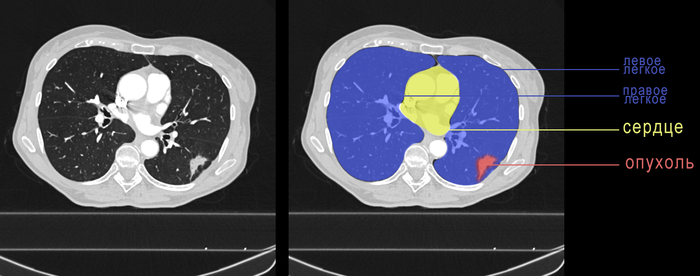

Пациентке 68 лет и у неё сложная история заболеваний. В 2015-16 годах пациентка прошла лечение рака левой молочной железы и прошла успешно. На сегодняшний день признаков рецидива болезни нет. В 2021 году пациентке удалили крупный зоб (увеличенная щитовидная железа). И вот, в 2023 году, кто-то из врачей всё-таки решил посмотреть повнимательнее контрольную КТ органов грудной полости, которую регулярно выполняют всем онкологическим пациентам.. А на этой КТ обнаружена крупная опухоль средостения (красный цвет), которая расположена между такими важными структурами, как правое лёгкое (розовый цвет), трахея (зелёный цвет), пищевод (голубой цвет), аорта (жёлтый цвет). Размер опухоли достигал 10 см.